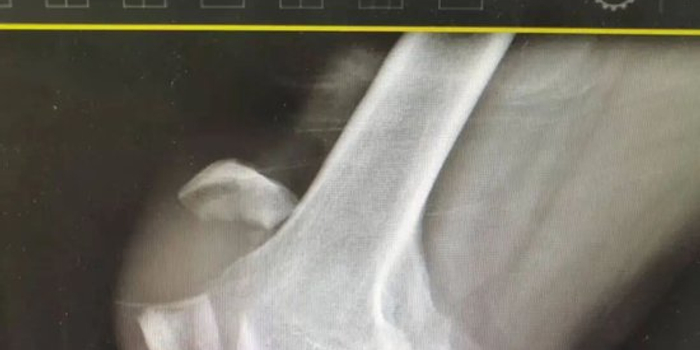

52岁的王先生意外摔倒,右侧膝盖重重着地,当即右膝剧痛难忍,肢体完全无法正常活动,家人见状紧急将其送至平原县人民医院急诊科就诊,经DR检查,诊断为右侧髌骨骨折。髌骨也就是大家常说的膝盖骨,是膝关节屈伸的重要支撑点,一旦骨折,若未能得到规范治疗,极易影响后续正常行走,甚至留下关节活动受限等后遗症,对日常生活带来诸多不便。明确诊断后,王先生随即被收治到创伤外一科接受专业治疗。

针对王先生病情,科室团队迅速制定周密手术方案,由杜明主任主刀,倪守洋医师协助,在硬膜外麻醉下为患者实施手术。术中探查发现,患者髌骨呈横形断裂且伴有碎骨,情况较为复杂。手术团队首先细致清理关节内血肿,随后在C臂透视机实时引导下,将骨折块进行精准对位,恢复关节面平整。随后,采用克氏针联合张力带钢丝进行内固定。该技术如同为骨折部位构建了一个坚固的 “内部脚手架” ,既能稳定骨折端,又能将分离的应力转化为促进愈合的压力,为骨骼愈合创造最优力学环境,最终实现骨折满意复位与可靠固定。